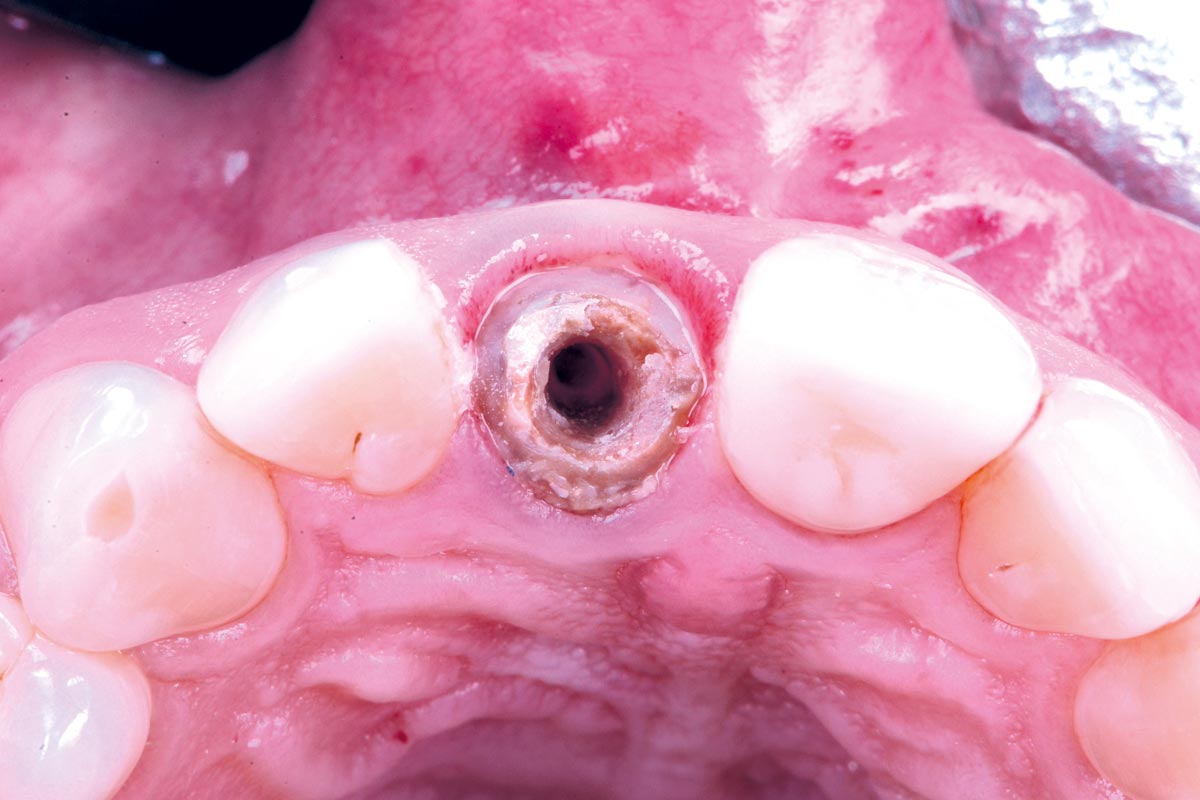

Initial view of the case. Discoloration of 1.1 and mild class I gingival recession